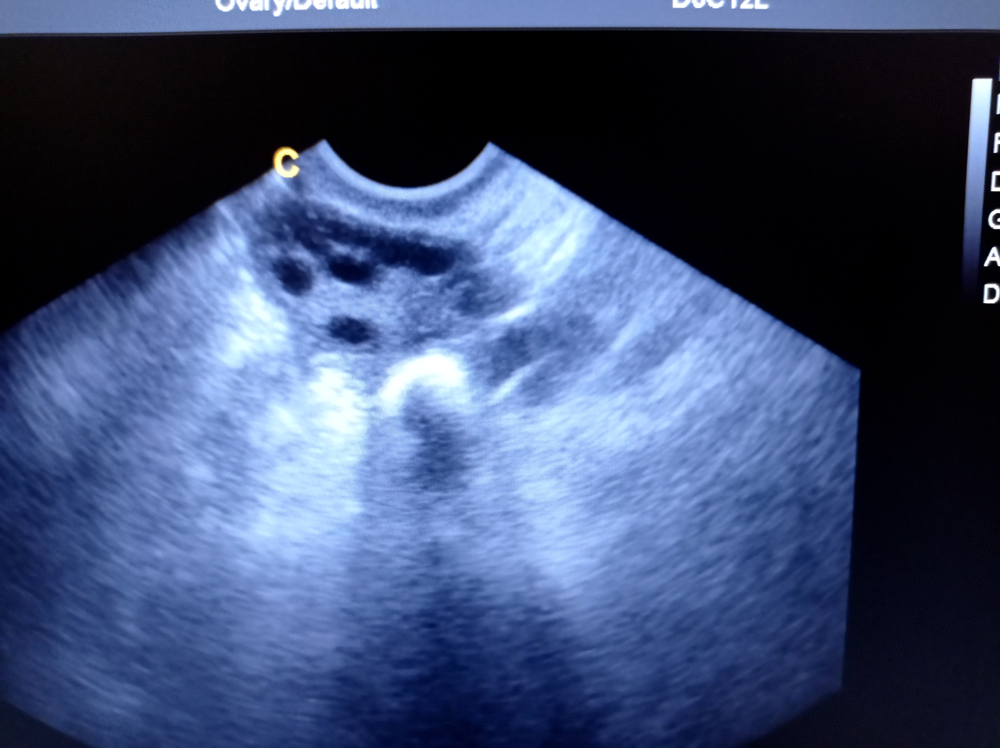

- поликистоз: определяется много мелких фолликулов по периферии, увеличивается объем, изменяется строма и гормональный фон;

Фотогалерея

Фолликулы – это «пузырьки», где созревают яйцеклетки. В нормальном состоянии их количество и диаметр меняются в течение менструального цикла: появляется доминантный фолликул, затем формируется желтое тело. Если фолликулов слишком много и они мелкие, это может свидетельствовать о поликистозе или гормональных нарушениях. Интерпретировать картину должен гинеколог по дню цикла и вашим симптомам.